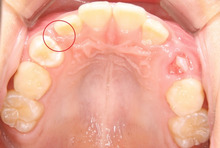

中学生になった 彼の口の中です。

赤い丸印に きちんと犬歯が入りました。

きれいでしょ!

装置はたった2つ。

下の歯は、何もしてません。